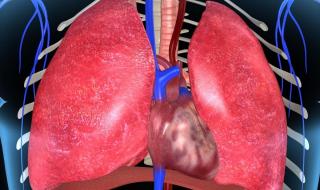

肺位于胸腔,心脏两侧,上半部分的肺可以穿过上肋骨,下边与横膈膜相贴(当然有两层胸膜),肺集合是在心肺之间循环的肺动脉和肺静脉,是肺的功能性血管。另一种是营养血管,称为支气管动脉和静脉,起源于胸主动脉,紧贴支气管壁。它们沿支气管分支分布,滋养支气管壁、肺血管和肺部内脏胸膜。

肺位于人体胸腔里面,跟气管相连。《黄帝内经》中描述“喉下为肺,两叶白莹”。肺部连着咽喉、气管,整个胸腔都被肺充填,中间是心脏,再往下面是腹腔,通过膈肌隔开。很早就认识到肺很脆弱,被称为娇脏,很多原因比如受寒、劳累、感染都可以损伤到肺。所以平常需要加倍呵护,不让其受到感染,吸入过多粉尘和刺激性气体,如香烟。

肺是胸部的主要器官。人体的胸部由肩部和肋缘围成。在中间,纵隔分为胸腔的左右两侧。通俗的说法是,包裹在里面的肋骨是胸腔,主要内容是肺。人体的肺分为左肺和右肺。每个肺分为几个肺叶,一般左肺2个肺叶,右肺3个肺叶。这种生理叶对手术很有帮助。例如,如果累及肺叶的某一段,只需要切除该段,而不需要整个肺。

5、肺:肺是人体的呼吸器官,位于胸腔,左右各一,覆盖于心之上。肺有分叶,左二右三,共五叶。肺经肺系(指气管、支气管等)与喉、鼻相连,故称喉为肺之门户,鼻为肺之外窍。